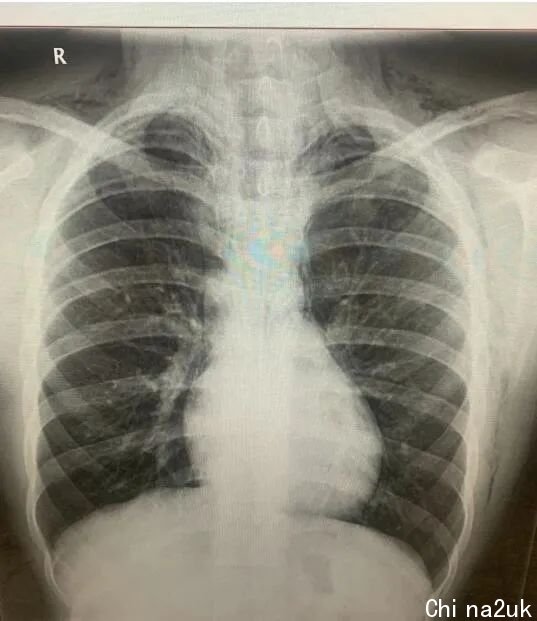

在病院,亚历克斯赶快向医生抵赖了本人吸食了笑气。因为亚历克斯的配合,他的病情很快就被确诊,发现是吸食笑气致使肺部决裂漏气。病情很重大,连医生都表现,假如不是送医及时,亚历克斯极可能曾经逝世了。

目前,亚历克斯还在病院承受医治,他的心脏和肺部四周有梗塞的空气,假如面罩无奈革除洁净的话,极可能要经过手术来革除。

“想一想就感觉惧怕,他差点就由于笑气挂了。他的肺上都泛起洞了。”